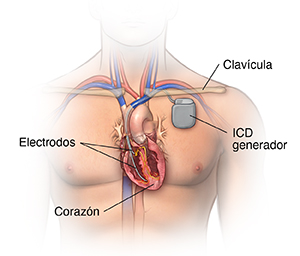

El desfibrilador automático implantable (DAI) es parecido al marcapasos, pero un poco más grande. Funciona casi como si fuera un marcapasos. Pero el DAI envía una descarga eléctrica que permite restablecer el ritmo cardíaco anormal.

Hay muchos dispositivos que combinan el marcapasos y el DAI en una sola unidad para las personas que necesitan ambas funciones. Después de que se emite la descarga, hay un modo de ritmo de "reserva" por si es necesario durante un tiempo breve.

El DAI tiene otro tipo de tratamiento para determinados ritmos rápidos que se llama estimulación antitaquicardia (ATP, por su sigla en inglés). Se trata de un impulso de marcha rápida para corregir el ritmo. En algunos casos, puede usarse en lugar de aplicar una descarga al corazón.

¿Cuáles son las partes de un marcapasos o un DAI?

Un marcapasos o un DAI típicos tienen tres partes principales:

Un generador de pulsos con batería sellada de litio. El generador de pulsos envía las señales eléctricas que hacen latir el corazón o envía una descarga eléctrica. La mayoría de los generadores también pueden recibir señales enviadas por el propio corazón y responder a dichas señales.

Un cable o más. Son cables flexibles y con aislamiento. Los cables conducen las señales eléctricas entre el corazón y el generador de pulsos. Un extremo del cable se conecta al generador de pulsos y el extremo del electrodo del cable se coloca en el corazón. En el caso del marcapasos biventricular, los cables se colocan en ambos ventrículos.

Electrodos. Se ubican en cada cable.

El proveedor de atención médica le hará una incisión pequeña debajo de la clavícula. Colocará el cable o los cables del marcapasos/DAI en el corazón a través de un vaso sanguíneo que pasa por debajo de la clavícula. Una vez que el cable esté en su posición, el proveedor de atención médica lo probará para asegurarse de que esté en el lugar correcto y funcione. A continuación, conectará el cable al generador (batería), que se coloca debajo de la piel a través de la incisión ya hecha. El proveedor de atención médica cerrará la incisión con puntos, grapas o pegamento quirúrgico (adhesivo) y colocará un vendaje. Una vez finalizado el procedimiento, tendrá un período de recuperación de varias horas.